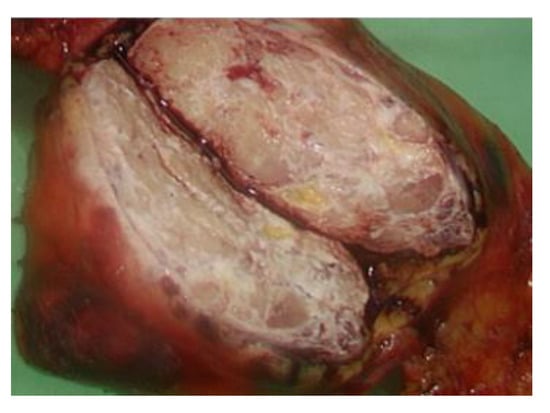

The serum carcinoembryonic antigen concentration was 0.92 ng/mL (normal range: 0.00–5.00 ng/mL), squamous cell carcinoma antigen level was 1.40 ng/mL (normal range: 0.00–2.10 ng/mL), alpha-fetoprotein level was 0.83 ng/mL (normal range for males: 0.00–10.00 ng/mL), carbohydrate antigen 19-9 level was 4.22 U/mL (normal range: 0.00–37.00 U/mL), and beta 2-microglobulin level was 2.72 mg/L (normal range: 1.00–2.40 mg/L). Video-assisted thoracoscopic surgery (VATs) tumor resection identified a mass measuring 7.2 cm × 5.6 cm × 4 cm in the anterior mediastinum (Figure 4) and two adjacent lymph nodes.

Figure 4. A 7.2 cm × 5.6 cm × 4 cm mass identified after operation of Video-Assisted Thoracoscopic Surgery.